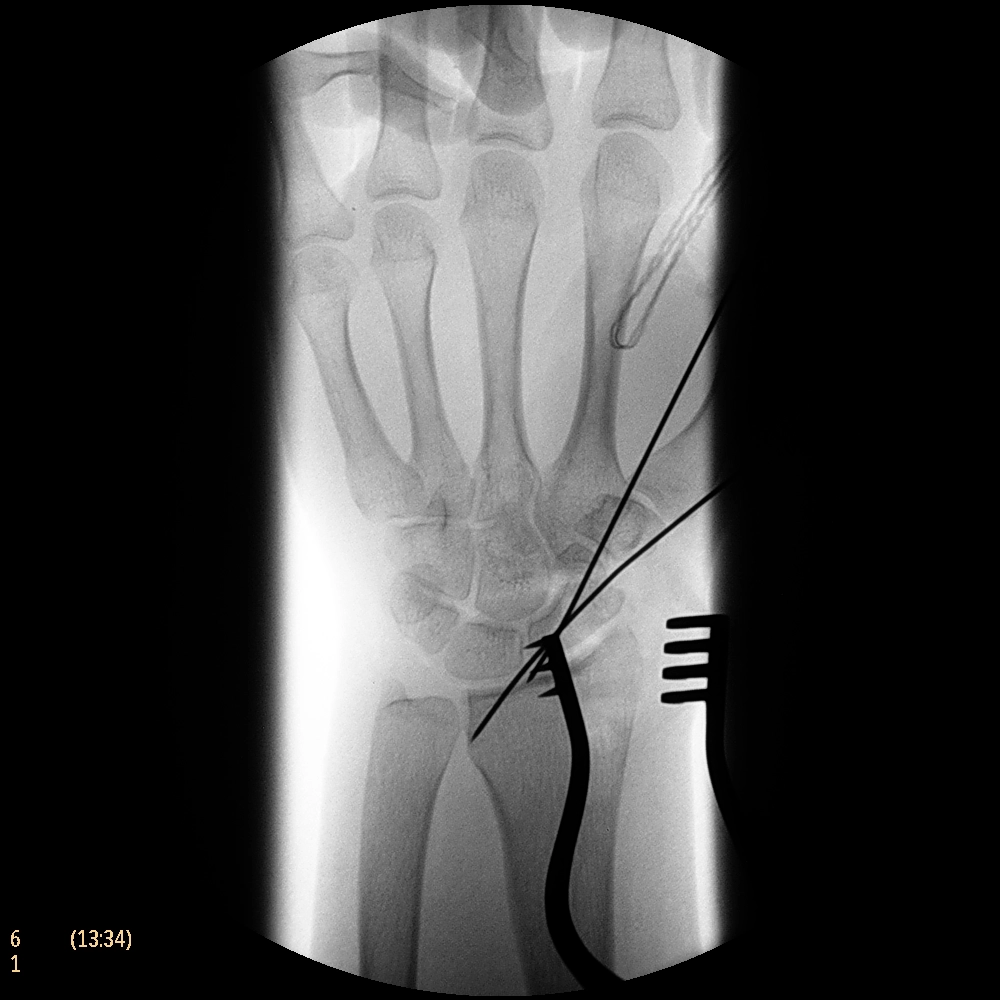

Система Philips BV Endura, рассчитанная на выполнение рутинных задач, расширяет возможности процедур на сосудах. Компактный размер 9-дюймового усилителя изображения обеспечивает маневренность для ортопедии и травматологии, а 12-дюймовый обеспечивает превосходный охват для выполнения сосудистых процедур, урологии и общей хирургии. Кроме того, мы увеличили угол поворота C-дуги до 135°, чтобы дать возможность получения проекций, необходимых для большинства процедур на сосудах.